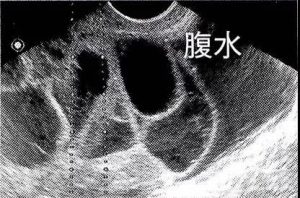

超声下可以看到肿大的卵巢和腹水的存在

严重者可引起血液浓缩、胸腹水、肝肾功能损坏、血栓形成、成人呼吸窘迫综合征,甚至死亡。